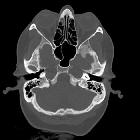

Petrous apex cephalocoele

Petrous apex cephalocoele (PAC) is a rare form of cephalocoele centered typically in the posterolateral part of Meckel cave with variable extension into the petrous apex. They can be unilateral or bilateral (commoner).

CT

- homogenously low density area is noted in the petrous apex with sharply defined margins